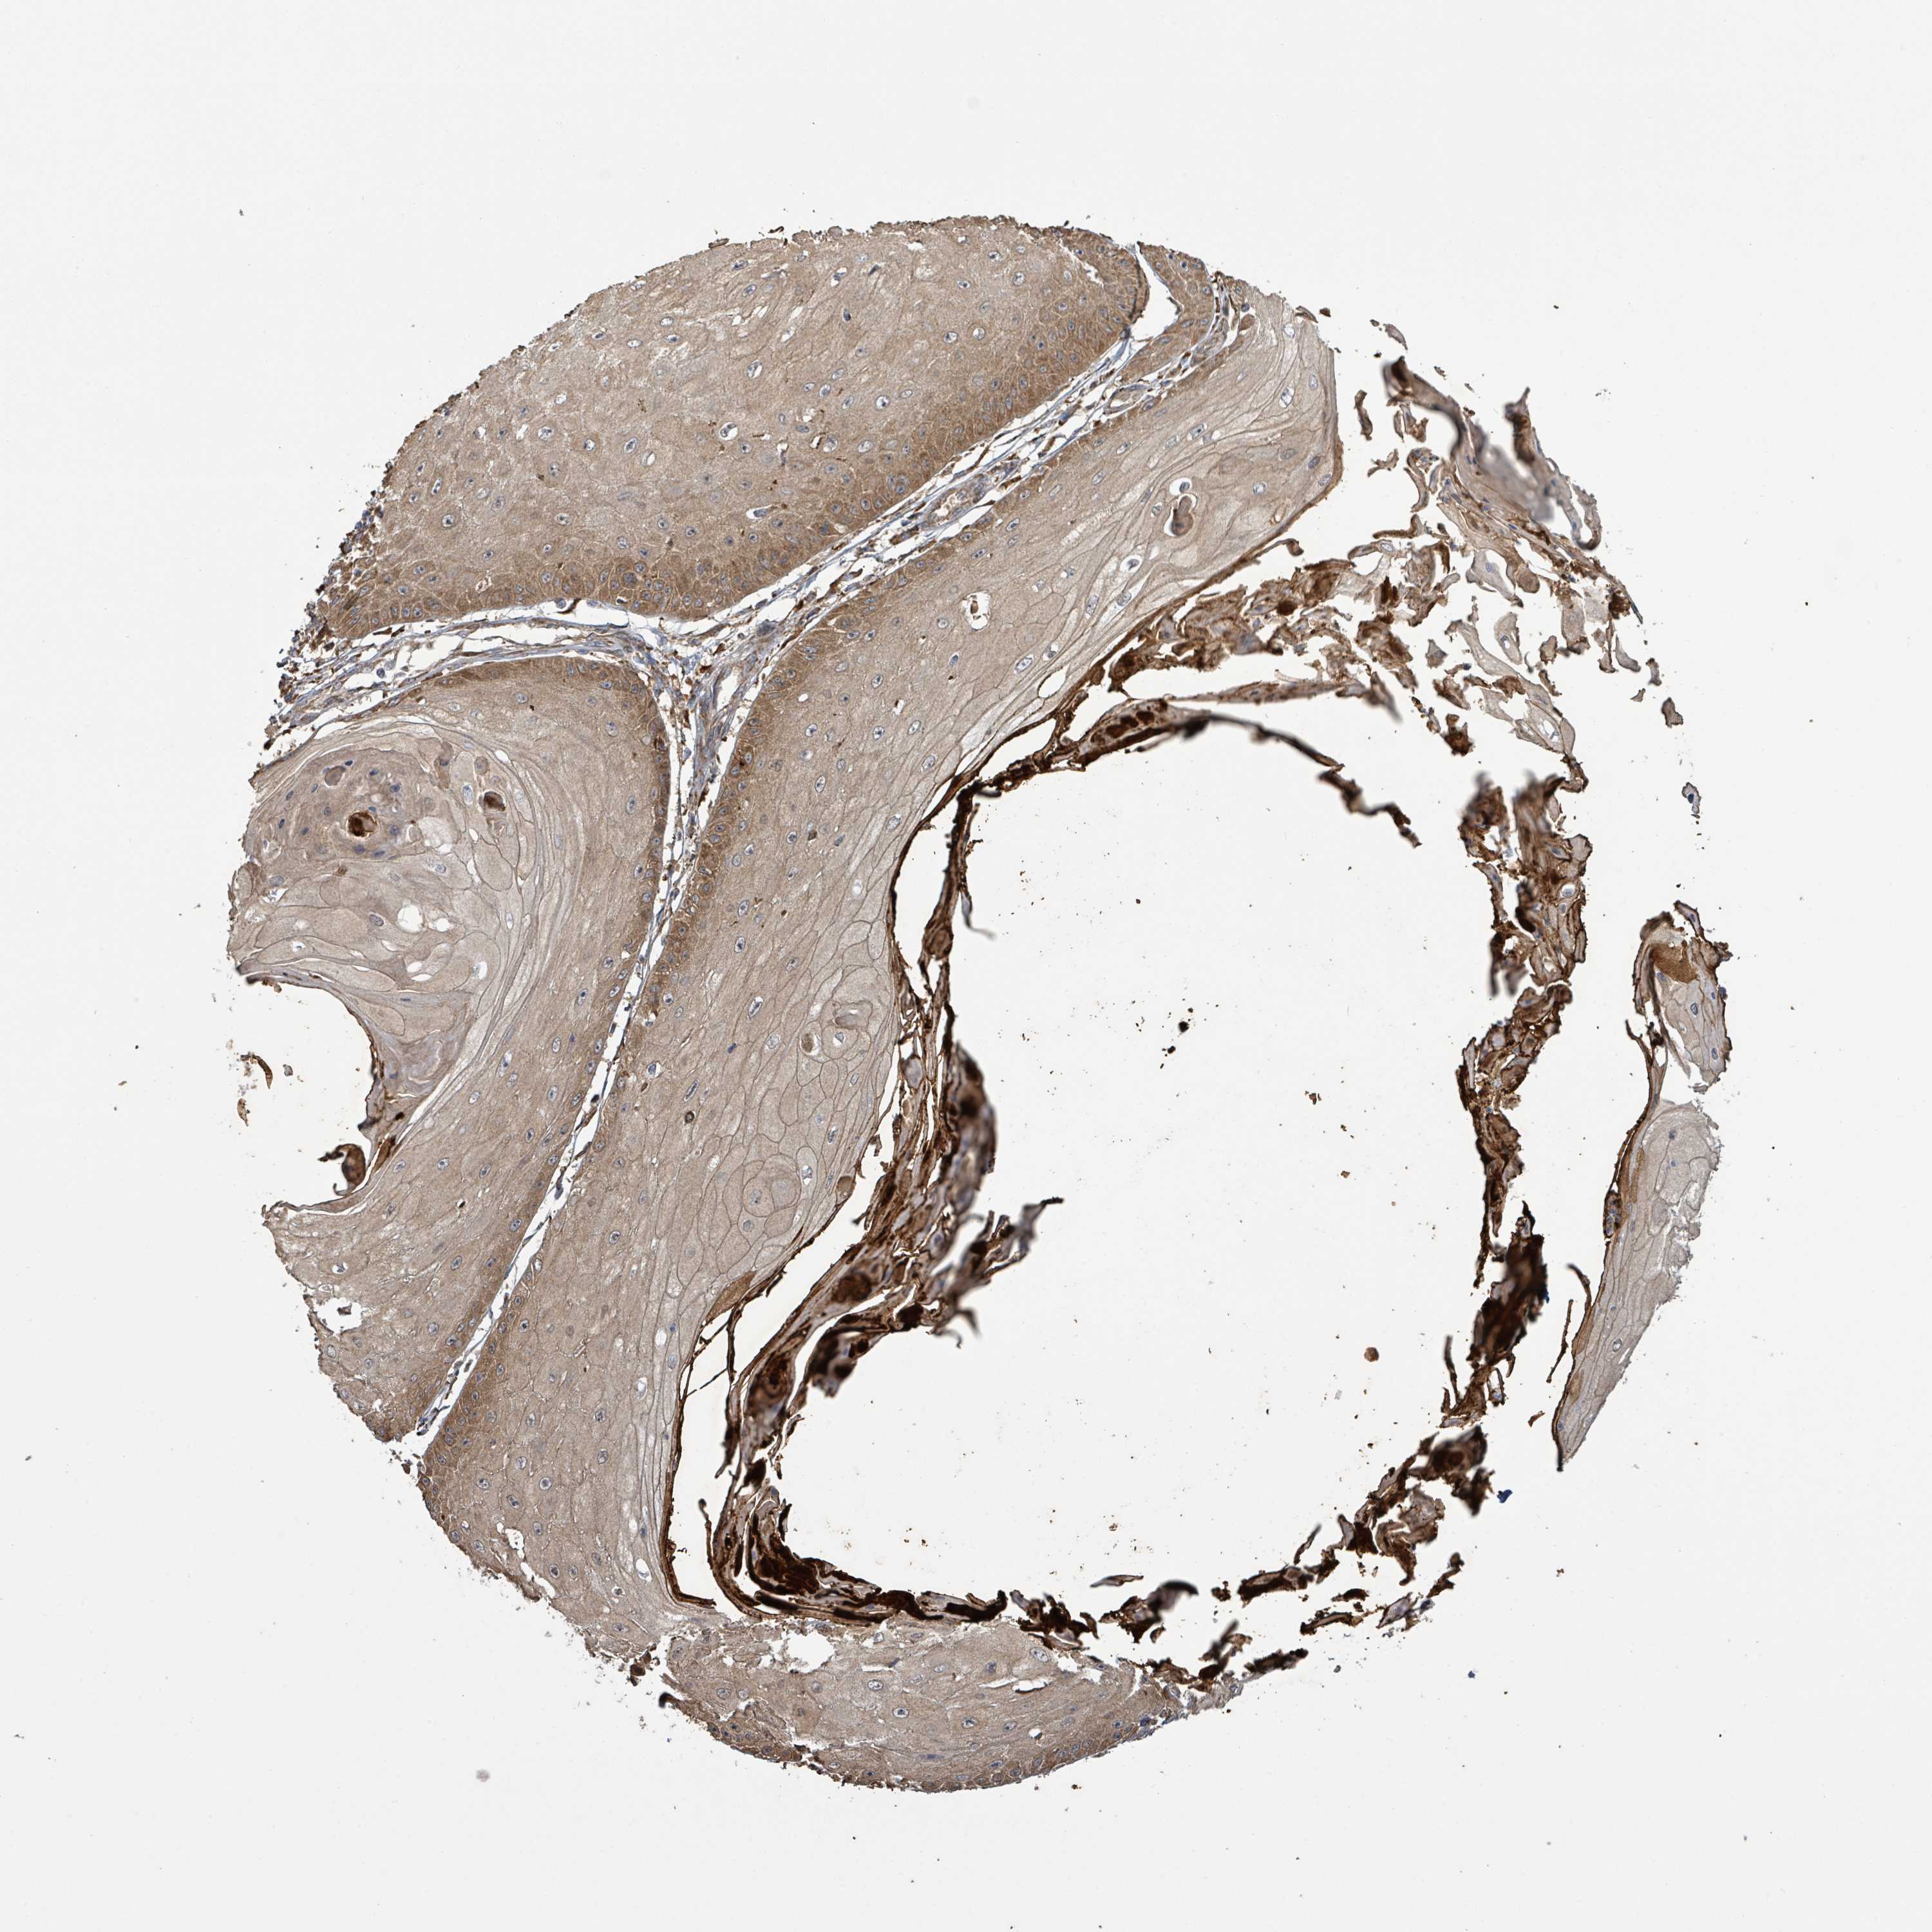

Basal cell and squamous cell cancer

SKIN CANCER - Protein expressioni

A mouse-over function shows sample information and annotation data. Click on an image to view it in a full screen mode. Samples can be filtered based on level of antibody staining by selecting one or several of the following categories: high, medium, low and not detected. The assay and annotation is described here.

Antibody stainingi

Antibody staining in the annotated cell types in the current human tissue is reported as not detected, low, medium, or high, based on conventional immunohistochemistry profiling in selected tissues. This score is based on the combination of the staining intensity and fraction of stained cells.

Each image is clickable and will lead to virtual microscopy that enables deeper exploration of all samples and also displays staining intensity scores, fraction scores and subcellular localization as well as patient and tissue information for each sample.

Squamous cell carcinoma, metastatic, NOS